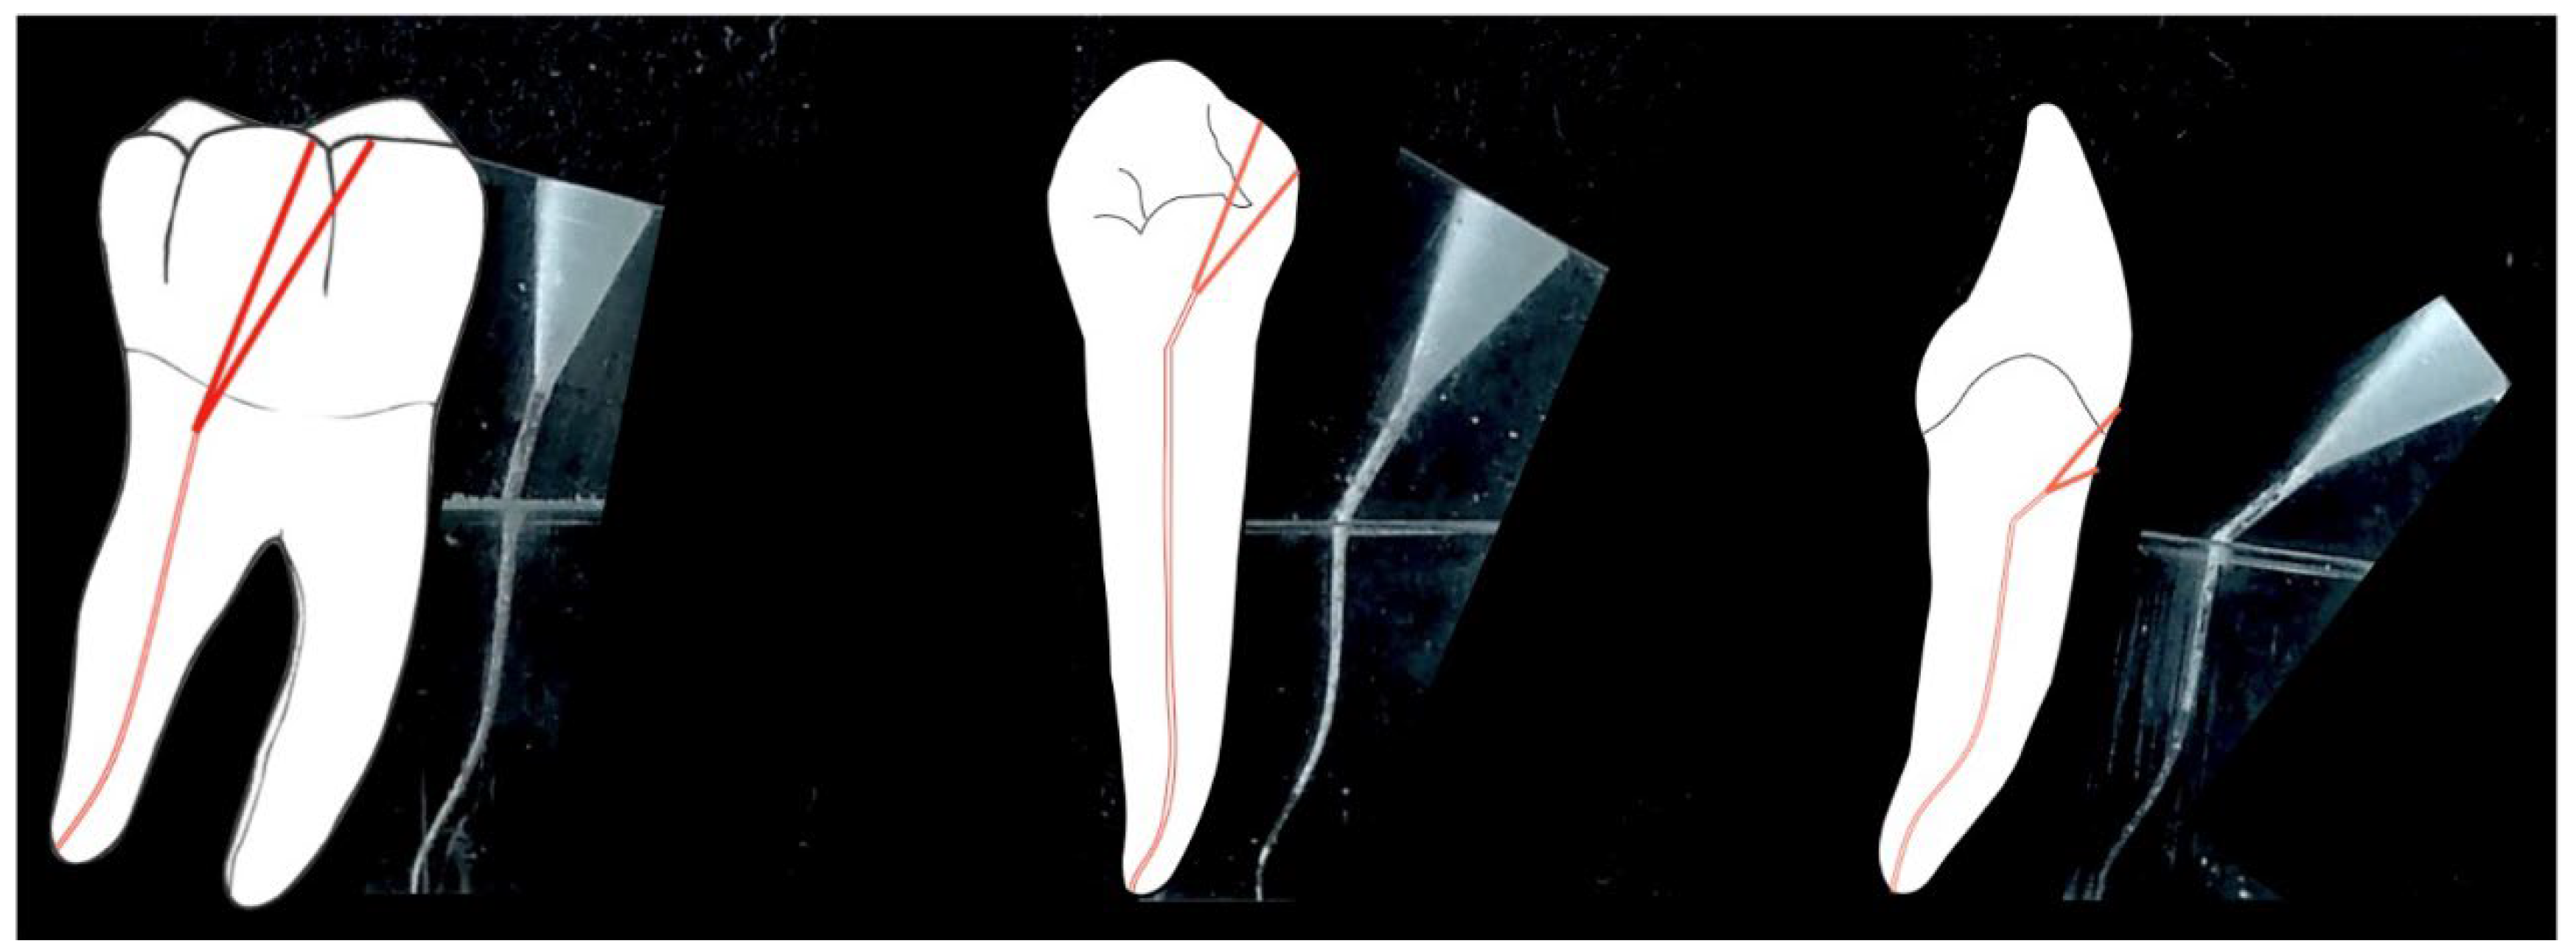

In contrast, microinvasive therapeutic approaches differentiate between three modified types of access: occlusal via a smaller opening (15° entrance angle), mesial/distal (via the cavitated caries defect) for premolars and molars (30° entrance angle) and cervical with wedge-shaped defects or root caries on anterior teeth and single-rooted premolars (45° access angle). Therefore, the aim of this work was (i) to create an in vitro model for the clinical simulation of these three different modified access types (Figure 2), (ii) to investigate the biomechanics within the framework of the instrumentation and (iii) to assess the volumetric loss of substance between four different preparation systems.

Simulated S-shaped root canals with a high degree of obliteration in acrylic polymer bodies with canal access angles of 15°, 30° and 45° (Figure 2) were randomized and blinded instrumented.

Figure 2. Clinically simulated root canals and canal access angles of 15°, 30° and 45°.